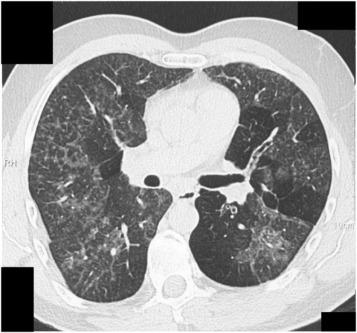

HP, an inflammatory lung disease, arises when repeated exposure to molds or other allergens causes the immune system to attack the lung tissue. Because the symptoms of HP—such as a chronic cough and shortness of breath—are alarmingly similar to other respiratory conditions, correctly pinpointing household mold as the culprit becomes a confusing bit in the diagnostic process. Recognizing these connections can be the key to early intervention and improved health outcomes.

Hypersensitivity pneumonitis (HP) is an inflammatory condition of the lungs that develops in some people after they repeatedly inhale certain antigens, including mold spores. In many cases, symptoms like chronic cough, shortness of breath, and fatigue mimic other respiratory conditions. For homeowners, understanding the origins of these symptoms is paramount because the usual culprits—such as outdoor pollutants—might be the last place you’d expect to find the source.

The challenge lies in the tricky parts of identifying the cause. Since HP can imitate other lung issues, healthcare professionals must rely on detailed environmental histories and less invasive tests, like bronchoscopy, to catch it early. In fact, one promising approach is focusing on the home environment—a space that offers both comfort and hidden dangers.